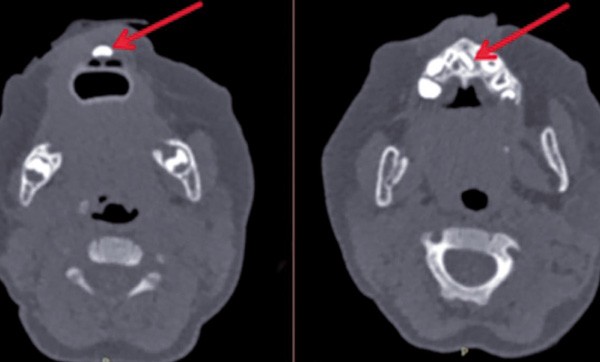

Un scanner, précédemment réalisé à la demande du pédiatre, objective une formation dentaire médiane ainsi que la présence d’un germe unique et médian d’incisive centrale permanente (fig. 3). En outre, il permet d’écarter l’hypothèse d’une fente palatine sous-muqueuse ou d’une sténose des orifices piriformes.